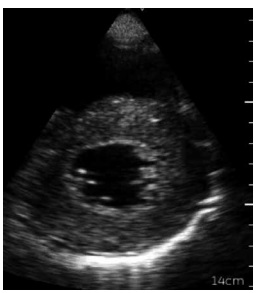

Considere-se a imagem a seguir.

Assinale a alternativa que apresenta a janela ecocardiográfica à qual a imagem corresponde.